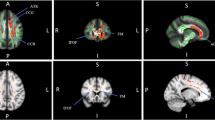

Between-group difference of the nodal strength was observed in the right inferior parietal lobule (IPL) (Fig. 3). Amusics exhibited significantly higher nodal strength in the right IPL region compared to controls (p = 0.0004). No significant results were found in other nodes or other nodal properties. With regards to the group differences under multiple thresholds (sparsities) of λ, Cp, and nodal strength of IPL, see Supplementary materials for detail. As shown in Supplementary materials, apparently, the group differences on these measures remain the same regardless of the specific tested threshold level.

(A) The right inferior parietal lobule in which the amusics showed significantly greater nodal strength than the controls (highlighted in blue). (B) Nodal Strength of the area under curve (AUC) of the amusics and the controls. Error bar represents standard error. *p < 0.05. Figures 3A and4 were plotted using an in-house software BrainNet Viewer64. http://www.nitrc.org/projects/bnv.

The network hubs with high nodal strength (at least 1 SD higher than the mean AUC of nodal strength) in the amusics (A) and the controls (B), with nodal size indicating the corresponding normalized AUC of the nodal strength. PCUN, Precuneus; STG, Superior temporal gyrus; INS, Insula; FFG, Fusiform gyrus; ROL, Rolandic operculum; DCG, Median cingulate and paracingulate gyri; OLF, Olfactory cortex; CAU, Caudate nucleus; ACG, Anterior cingulate and paracingulate gyri; R, right; L, left.

The inferior parietal lobe plays an important role in music processing34. As shown in Fig. 3A, the area with increased nodal strength in the amusic group relative to the control group resides mainly in the supramarginal gyrus of the inferior parietal region. The supramarginal gyrus has been implicated in perception tasks such as musical discrimination for both adults35 and children36, pitch memory37, and rhythm processing38. In addition to perception, the supramarginal gyrus also underlies music production39. Furthermore, the inferior parietal lobe in general are specifically involved in music memory40,41,42. The impairment of some of these functions is generally linked to amusia. The increase in nodal strength in this area might thus reflect a structural alteration of compensatory nature due to long-term functional adaptation to the compromised pitch-related processes in amusics.